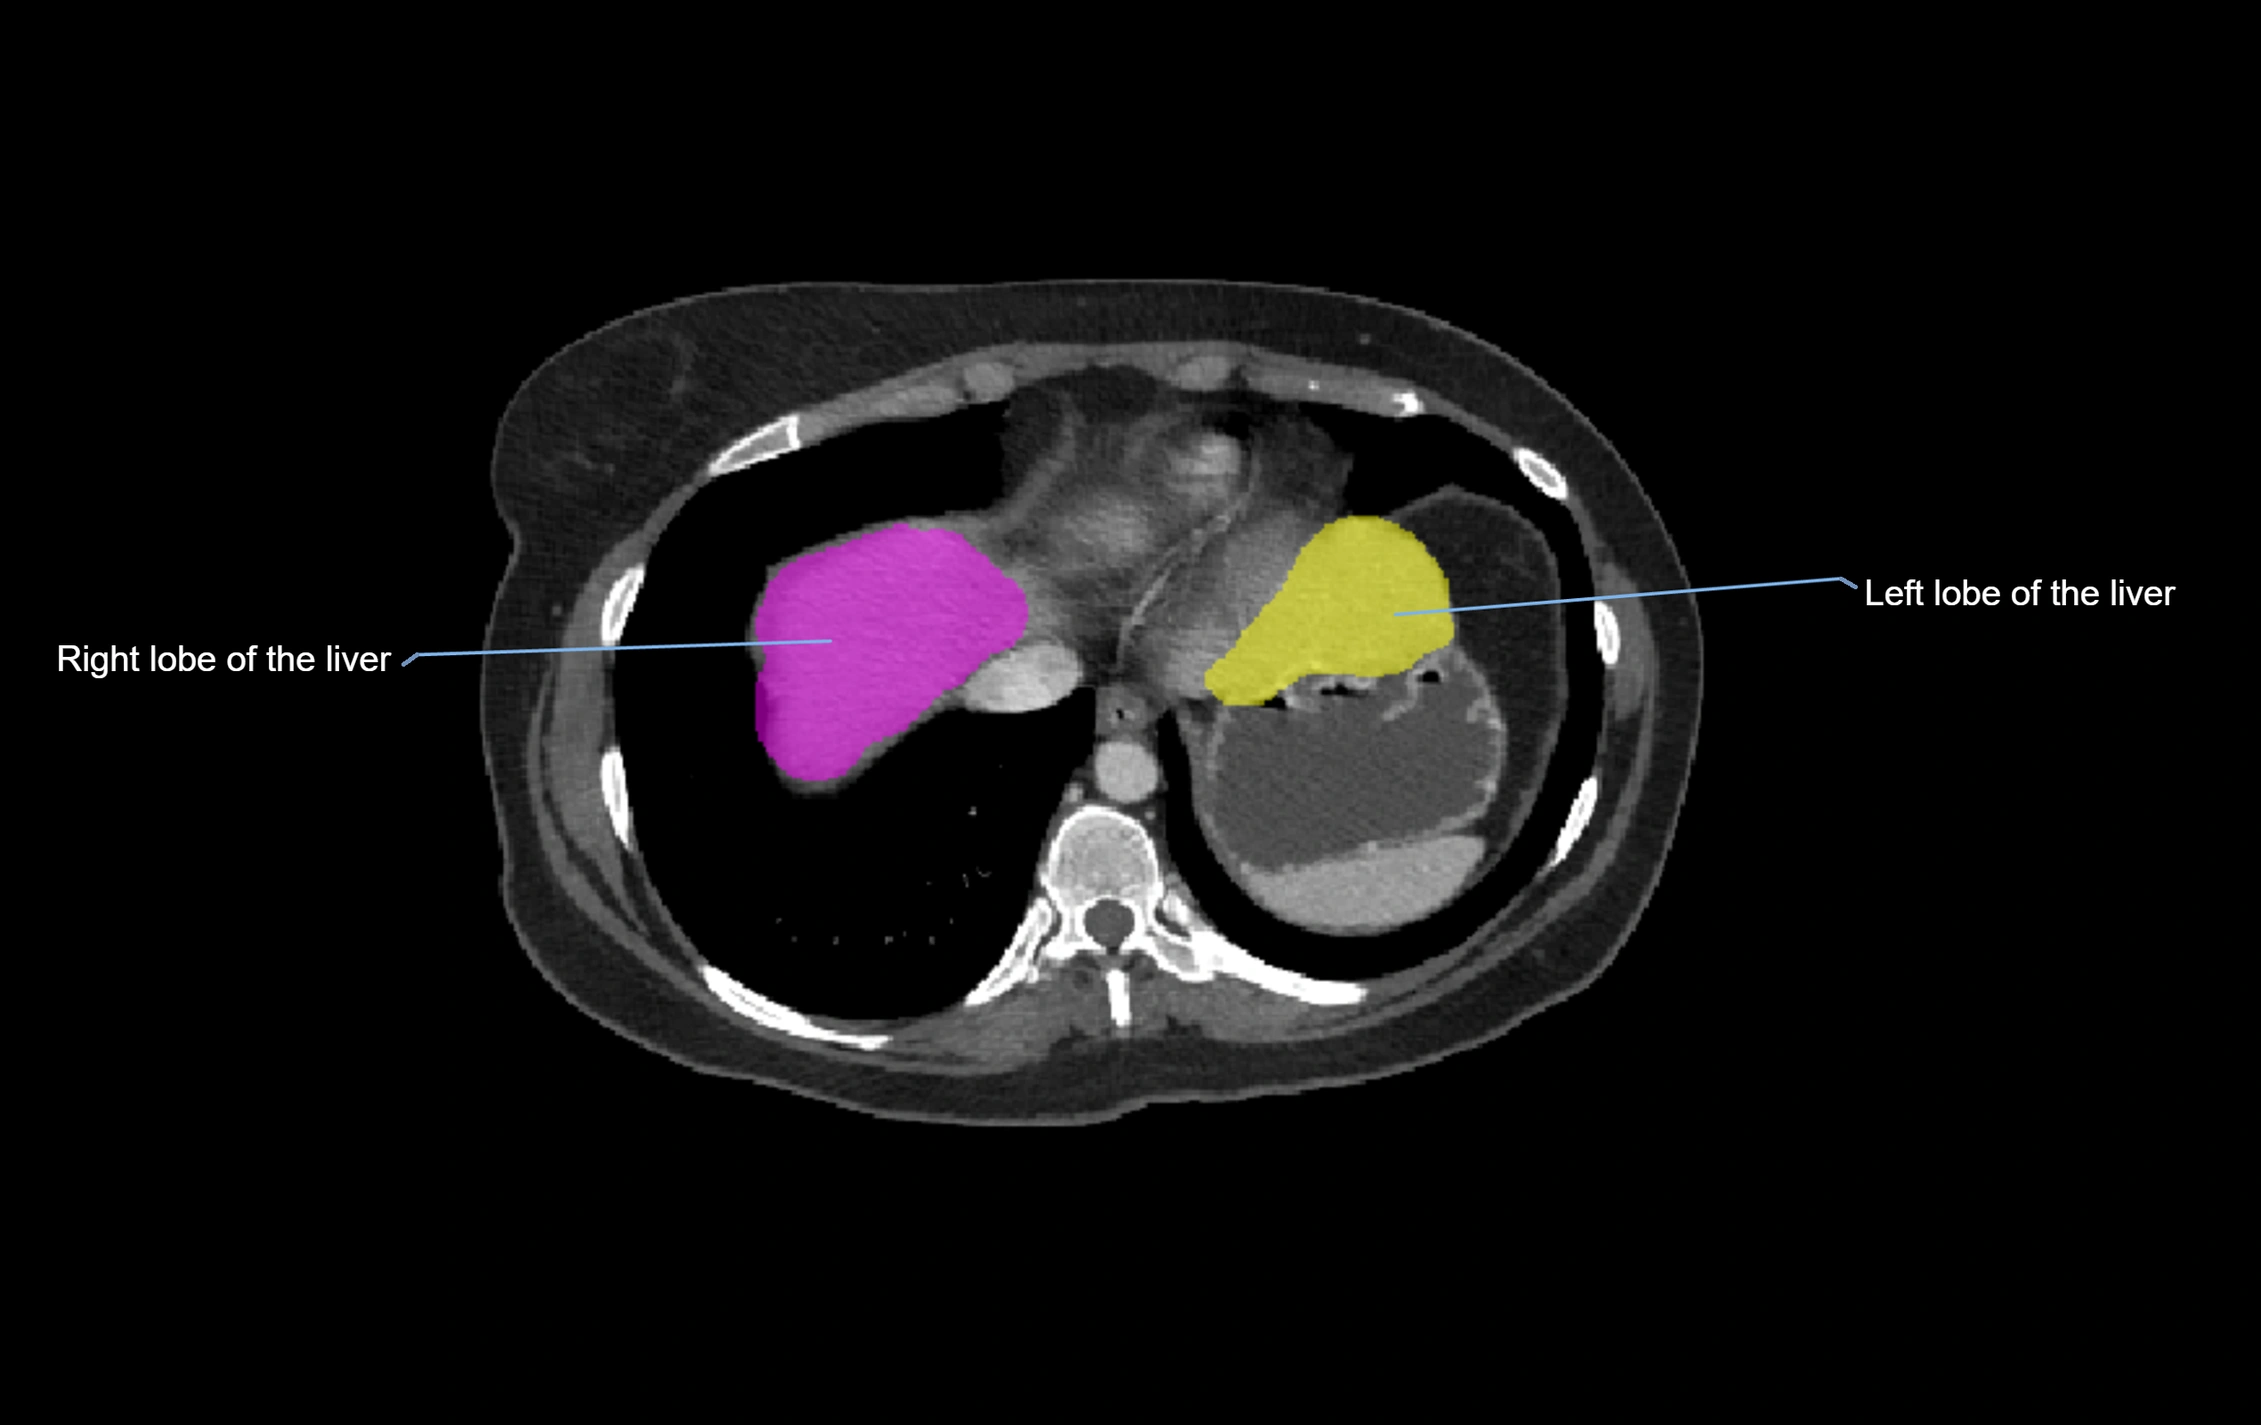

CT Appearance

CT Pre-Contrast:

• Caudate lobe appears as a soft-tissue density, isodense to the rest of the liver

• Enlargement may be appreciated in cirrhosis or Budd–Chiari syndrome

MRI image

image